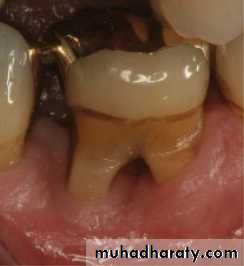

Cervical Enamel Projections

Grade I: The enamel projection extends from the cementoenamel junction of the tooth toward the furcation entrance.Grade II : The enamel projection approaches the entrance to the furcation. It does not enter the furcation, and therefore no horizontal component is present.

Grade III : The enamel projection extends horizontally into the furcation.